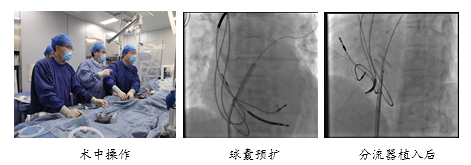

手术是在局部麻醉下进行的,患者全程清醒。唐熠达主任一边做手术一边言语安慰吴阿姨让她不要紧张。手术过程中,通过对肺动脉压力、左房压和右房压进行准确测量和计算,医生们为患者选择了最合适的分流器型号,并成功地进行了植入。

术后显示:分流器固定稳定、位置良好,分流器的诊疗效果符合预期目标。手术顺利结束,用时不到30分钟。